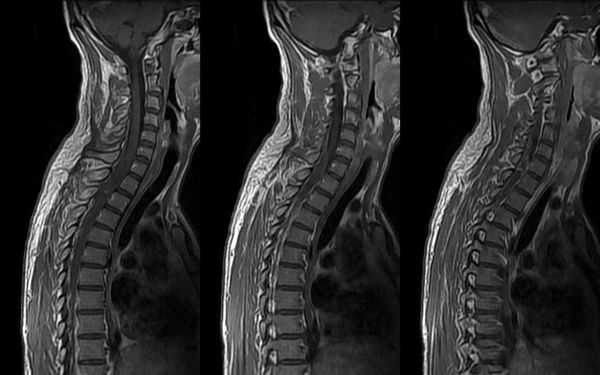

МРТ шеи: оценка спинного мозга (сагиттальная плоскость, Т2 последовательность)

МРТ шейного отдела позвоночника - высокоинформативный неинвазивный способ диагностики, использующий магнитное поле и компьютерную обработку для получения изображений. Преимущества магнитно-резонансного сканирования в сравнении с рентгеновскими методами обследования - отсутствие лучевого воздействия и возможность детализации патологических процессов в мягких тканях: на томограммах видны хрящи, синовии, связки, межпозвонковые диски, спинной мозг, нервы. Если в организме человека нет металлических составляющих или функционирующих устройств с ферромагнитными свойствами, негативные последствия, включая отдаленные, после проведения диагностической процедуры отсутствуют.

МРТ шеи: перелом зубовидного отростка с невральной компрессией (сагиттальная плоскость, Т2 последовательность, STIR)

МРТ позвоночника назначают, если предыдущие способы обследования - КТ, рентгенография, УЗИ с допплером - продемонстрировали неоднозначные результаты или характер выявленных изменений требует уточнения, для оценки индивидуальных анатомических особенностей перед планируемой операцией, в рамках динамического наблюдения за болезнью на фоне лечения. Что показывает МРТ шеи:

МРТ шейного отдела позвоночника: оценка лордоза, сагиттальная плоскость, Т2 последовательность

- искривления позвоночника - кифоз, лордоз, сколиоз;

МРТ шеи: оценка сколиоза (коронарная плоскость, Т2 последовательность, STIR)

Боль в шее может быть вызвана проблемой в самом позвоночнике или в окружающих его мышцах. Наиболее часто дискомфорт в данной анатомической области обусловлен остеохондрозом, грыжей или протрузией межпозвонковых дисков, компрессией нервно-сосудистых пучков, иннервирующих спинной мозг, невралгией. Перед тем, как сделать выбор в пользу МРТ, врач оценивает характер боли и ее локализацию. Неприятные ощущения в области передней части шеи чаще свидетельствуют о заболевании трахеи, гортани, щитовидной железы, воспаленных лимфатических узлах, осложнениях со стороны уха. Для постановки диагноза в описанных ситуациях иногда достаточно проведения физикального и инструментального осмотра, ультразвуковой сонографии. Если пациент предъявляет жалобы на боль в задней поверхности шеи, усиливающуюся при повороте или наклоне головы, прострелы, ограничение в подвижности - для обнаружения проблемы обосновано сделать МРТ шейного отдела позвоночника. Магнитно-резонансное сканирование показывает структурные изменения в области интереса. Если боль носит функциональный характер, например, сопутствует миозиту, лучевая диагностика будет малоинформативна.